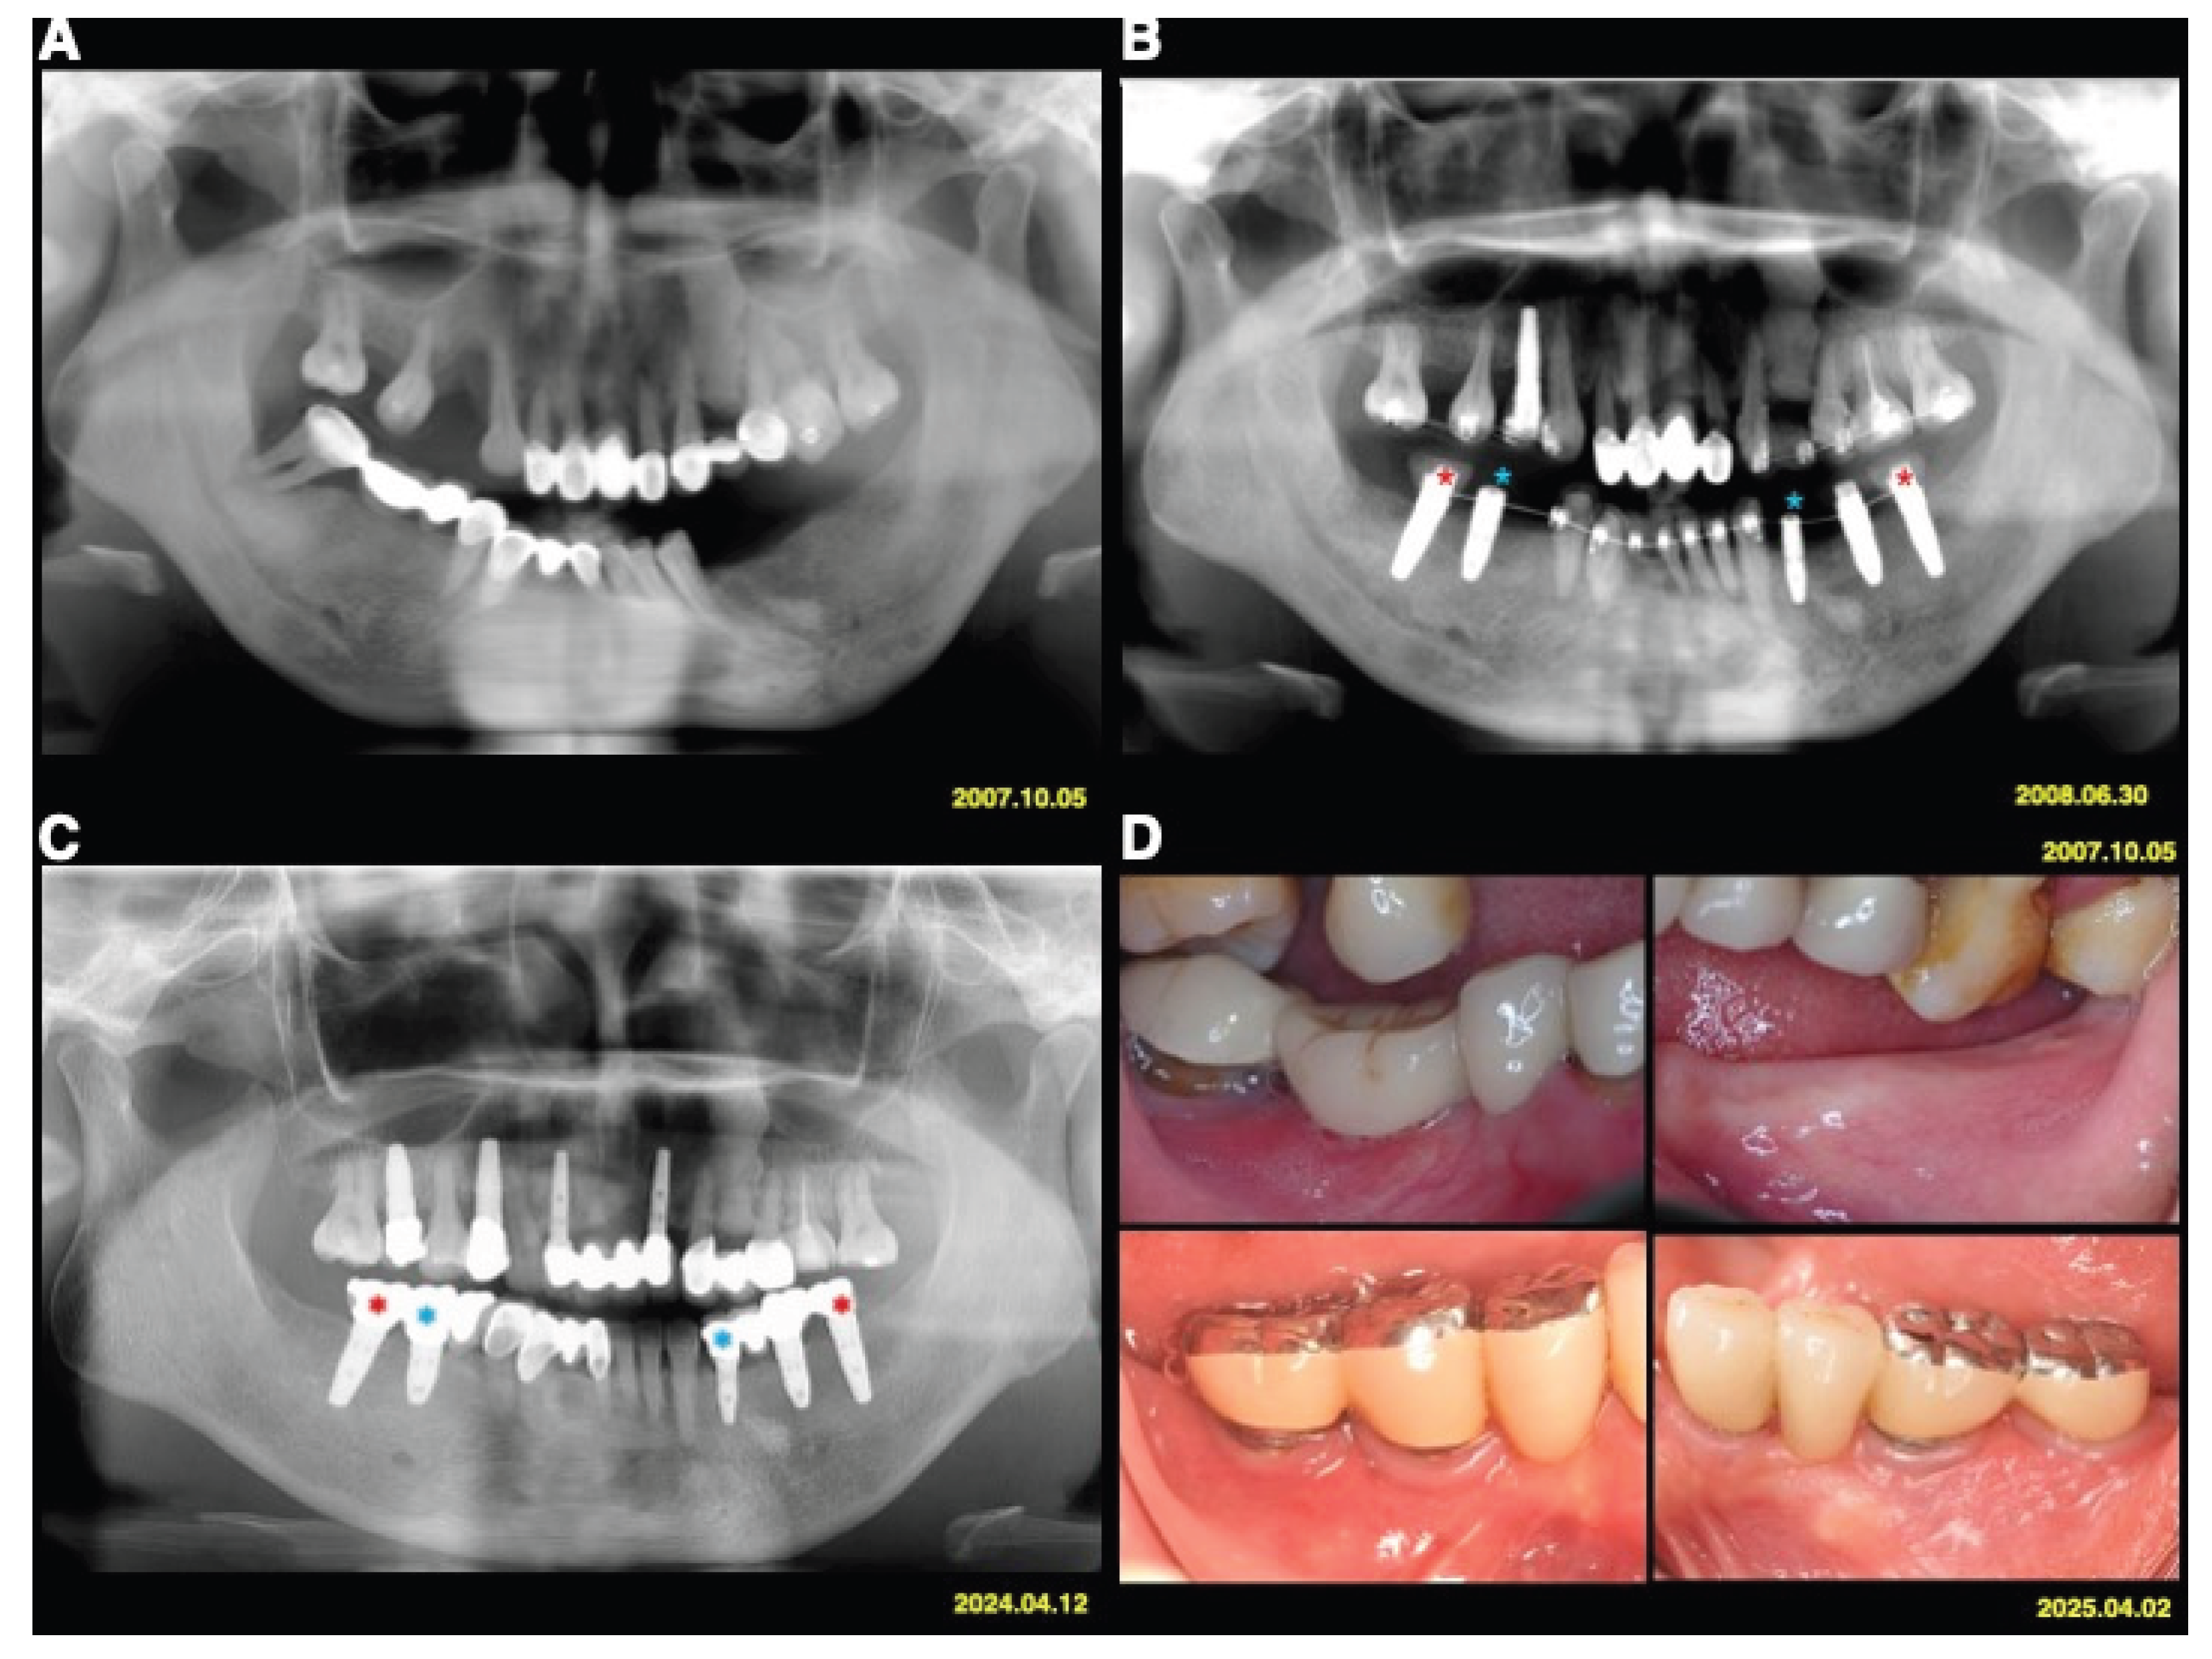

The test implants served as absolute orthodontic anchorages to facilitate molar uprighting, tooth retraction and realignment, or implant site development, whereas implants used exclusively for prosthetic purposes served as controls (Figure 1 and Figure 2). The use of implant anchorage significantly supported orthodontic treatment in patients with periodontally compromised dentition. A key advantage of this combined orthodontic-prosthetic approach was that the implants play a dual role, providing both anchorage and functional rehabilitation.

Figure 2. Case 2. (A) A 40-year-old female patient with stage IV periodontitis requested full-mouth reconstruction. (B) Dental implants were used for dual purposes: as orthodontic anchorage and as part of the oral rehabilitation of a periodontally compromised dentition. Test implants (red star) served as absolute orthodontic anchorage to facilitate retraction of the lower anterior teeth and implant site development, while implants used exclusively for prosthetic purposes (blue star) served as controls. (C) Radiographic findings from 2024 showed minimal periodontal and peri-implant bone loss. (D) Clinical outcomes 17.5 years post-treatment demonstrated healthy and stable peri-implant tissues.